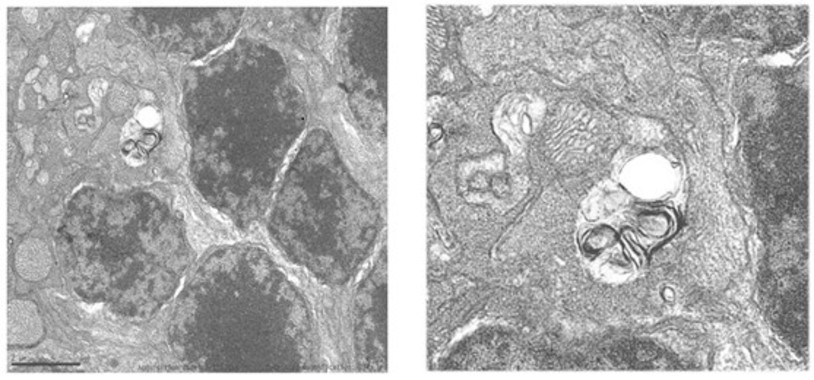

Deficiencia de ACOX2: Una alteración hereditaria en la síntesis de ácidos biliares identificada en un adolescente con hipertransaminasemia persistente

30/01/2017